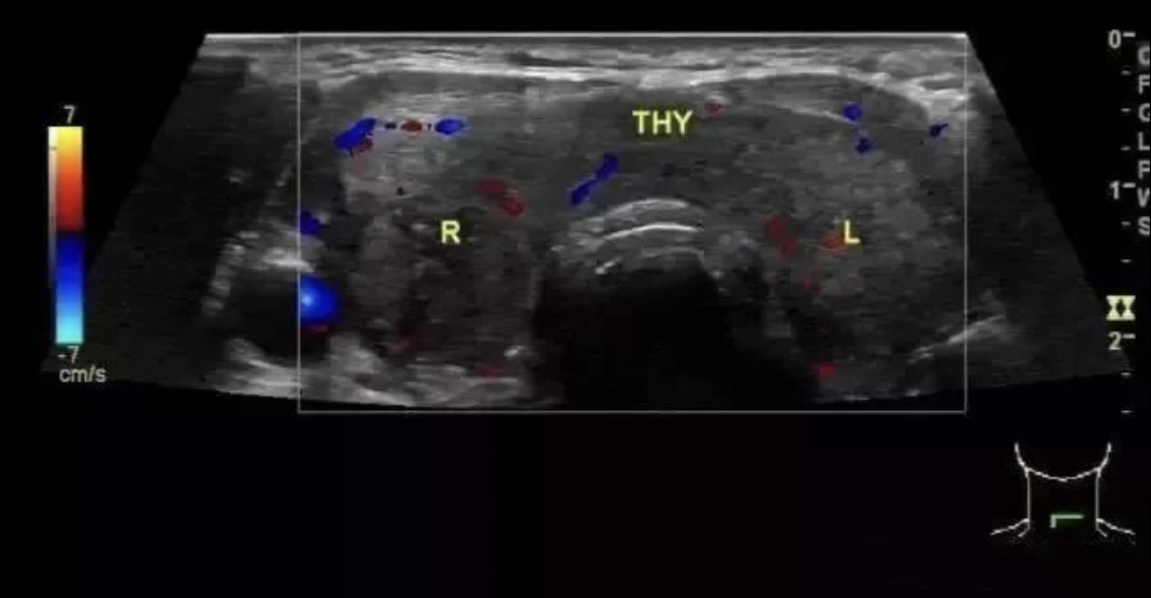

【超声检查】

1、两侧叶弥漫性对称性轻度增大,质硬,以侧叶前后径和峡部增大为主。

2、内部回声较正常减低,条索状强回声和散在细小低回声呈网格状。

3、CDFI:腺体内血流信号丰富,甲状腺上动脉血流速度中度增快,50-1000cm/s。

4、治疗后血流信号可能减少,但低回声不可逆。